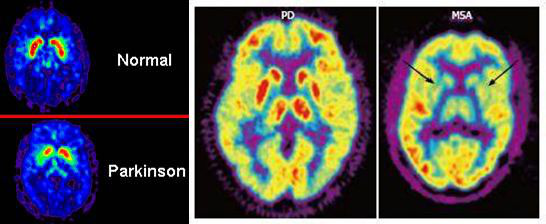

PET 是鑒別 PD 和 APS 的有用工具。保存基底節(jié)的代謝活性是 FDG-PET 中 PD 的一個重要特征,而 APS 基底節(jié)代謝活性明顯減低。

FDG-PET顯示PD基底節(jié)代謝活動得到保留,而MSA基底節(jié)代謝明顯減低